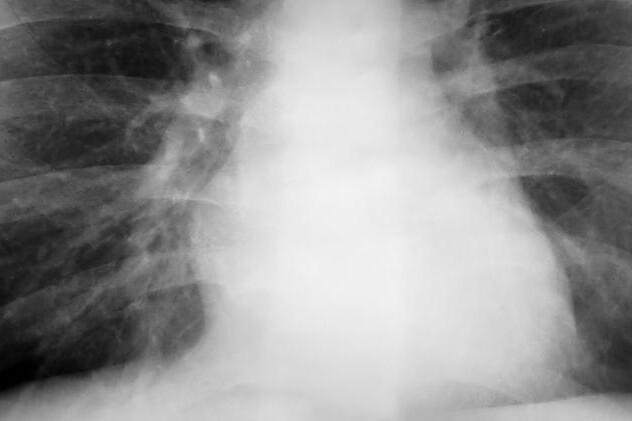

Diagnostika kardiomyopatie spočívá v pečlivé anamnéze s analýzou klinických projevů a samotným vyšetření lékařem. Při poslechu srdečního rytmu za pomocí fonendoskopu si lékař může všimnout arytmie, tedy nepravidelného rytmu srdce. Pro správnou diagnózu je nutné použít i zobrazovacích metod, jako je rentgen plic, či echokardiografii, tedy ultrazvuk srdce, na kterém můžeme pozorovat změny srdeční stěny. Jelikož se příznaky podobají ischemické chorobě srdeční, je nutné k jejímu vyloučení provést koronarografii, tedy zobrazení cév pod rentgenovými paprsky po jejich náplni kontrastní látkou.